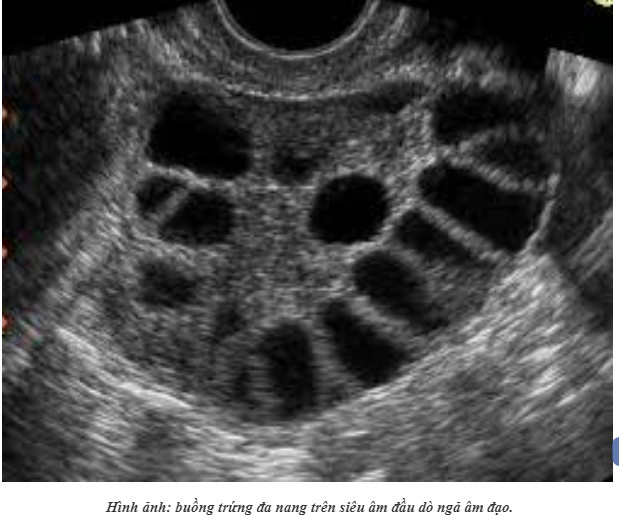

HỘI CHỨNG BUỒNG TRỨNG ĐA NANG THEO QUAN ĐIỂM Y HỌC CỔ TRUYỀN

Hội chứng buồng trứng đa nang (Polycystic ovary syndrome – PCOS) là bệnh lý rối loạn nội tiết, phóng noãn thường gặp ở phụ nữ lứa tuổi sinh sản với các triệu chứng đa dạng: rối loạn kinh nguyệt, cường androgen lâm sàng và cận lâm sàng, rối loạn chế tiết các hormon, có hình ảnh buồng trứng đa nang trên siêu âm..[1]